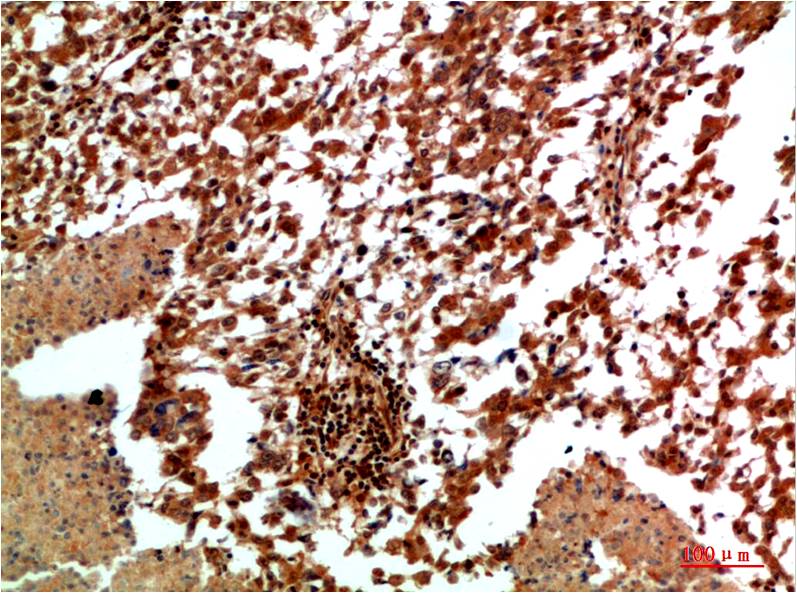

| Dilutions: | WB 1:500-1,000 IHC 1:100-200 |